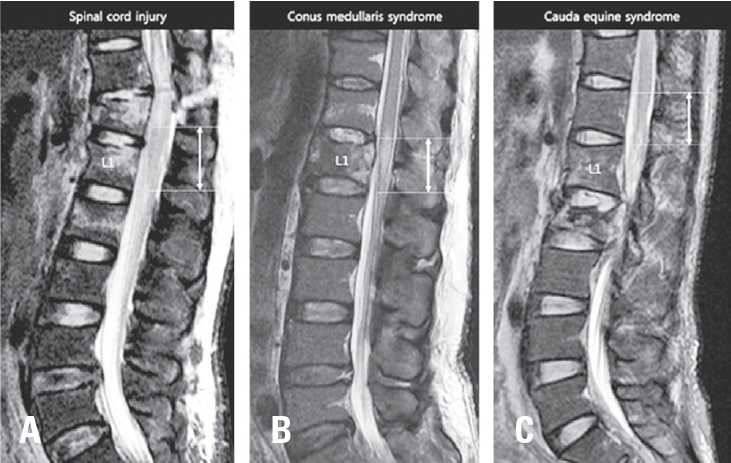

MRI Signal Characteristics of Conus Medullaris Aids Prediction of Bladder Outcome in Traumatic Conus Medullaris Syndrome

Han-Dong Lee J Adv Spine Surg 2025;15(2):104-113.